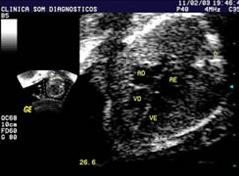

Esta es una prueba indicada para detectar de manera temprana alguna posible anomalía en el corazón del futuro bebé. Se realiza sobre la décimo tercera semana de embarazo y gracias a un estudio realizado con ultrasonidos, se puede evaluar en que situación se encuentran las arterias coronarias y las cuatro cavidades existentes en el corazón.

Realizar una ecocardiografía precoz permite diagnosticar y tratar a tiempo este tipo de anomalías, algo fundamental para garantizar el bienestar del niño. Los resultados de esta prueba garantizan un 95% de éxito en el diagnóstico, el resto necesita nuevamente realizar una segunda prueba cuando la primera no ha sido determinante. Esta prueba suele realizarse a todas las futuras mamás cuando el bebé tiene una alteración en el flujo sanguíneo.